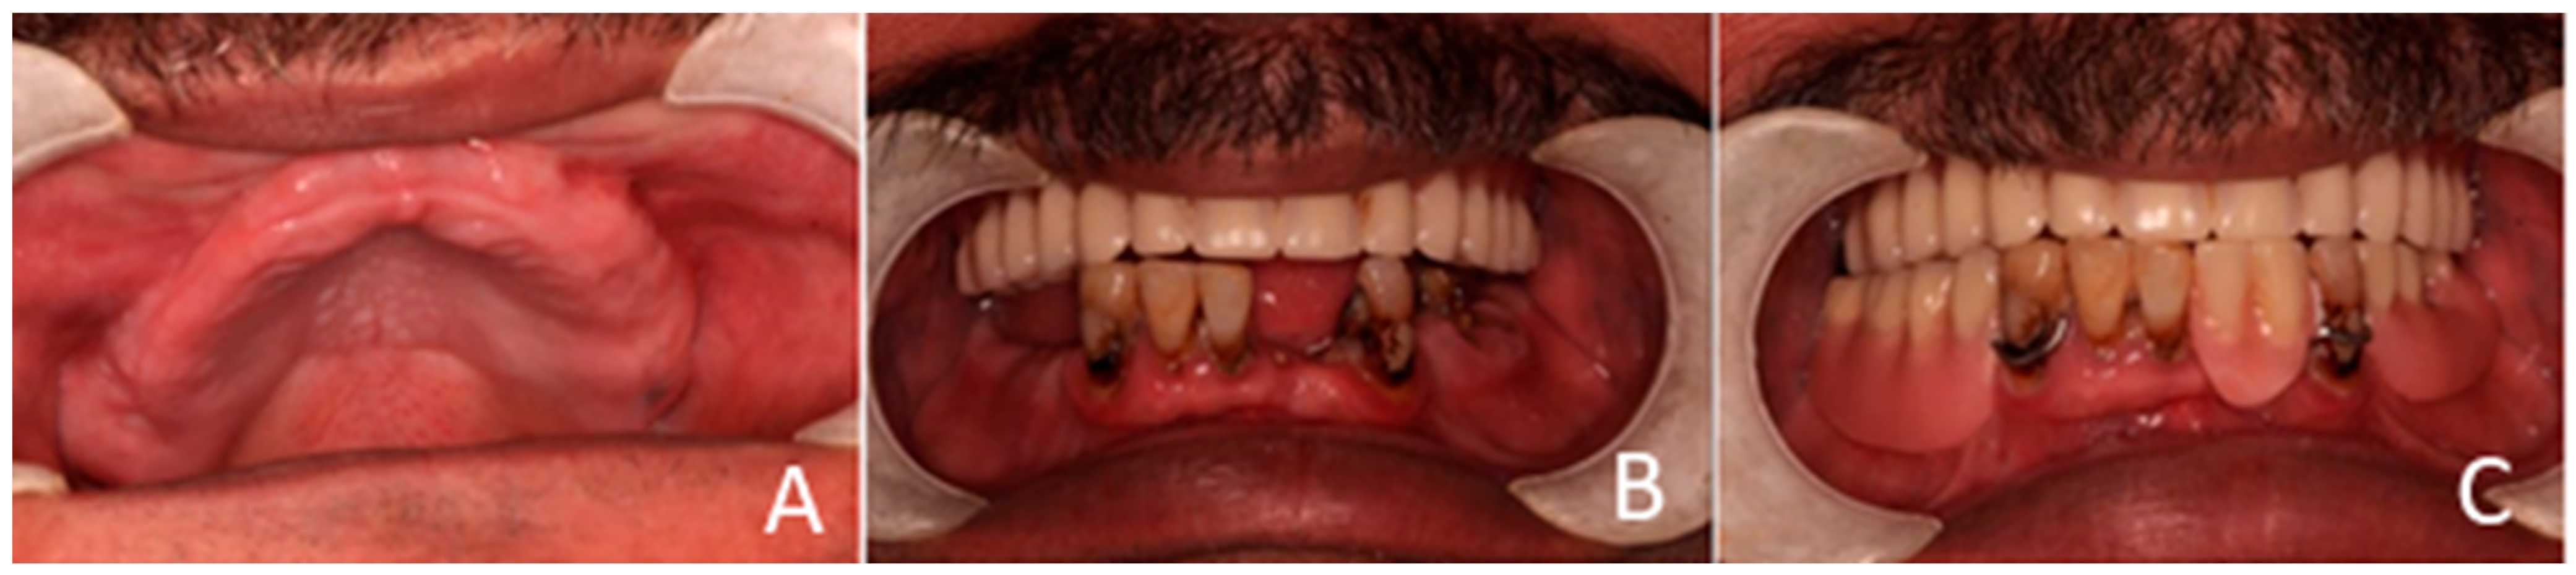

The clinical dental assessment, at the time, indicated a completely edentulous maxilla and a partially edentulous mandible. The residual mandibular teeth exhibited periodontal compromise, classified as Grade 3 mobility according to the Miller Classification, with multiple cavities and a poor overall prognosis (Figure 1).

Figure 1. Preoperative oral condition. (A) The edentulous maxilla. (B) Partially edentulous mandible. (C) Maxillary denture and mandibular partial denture.